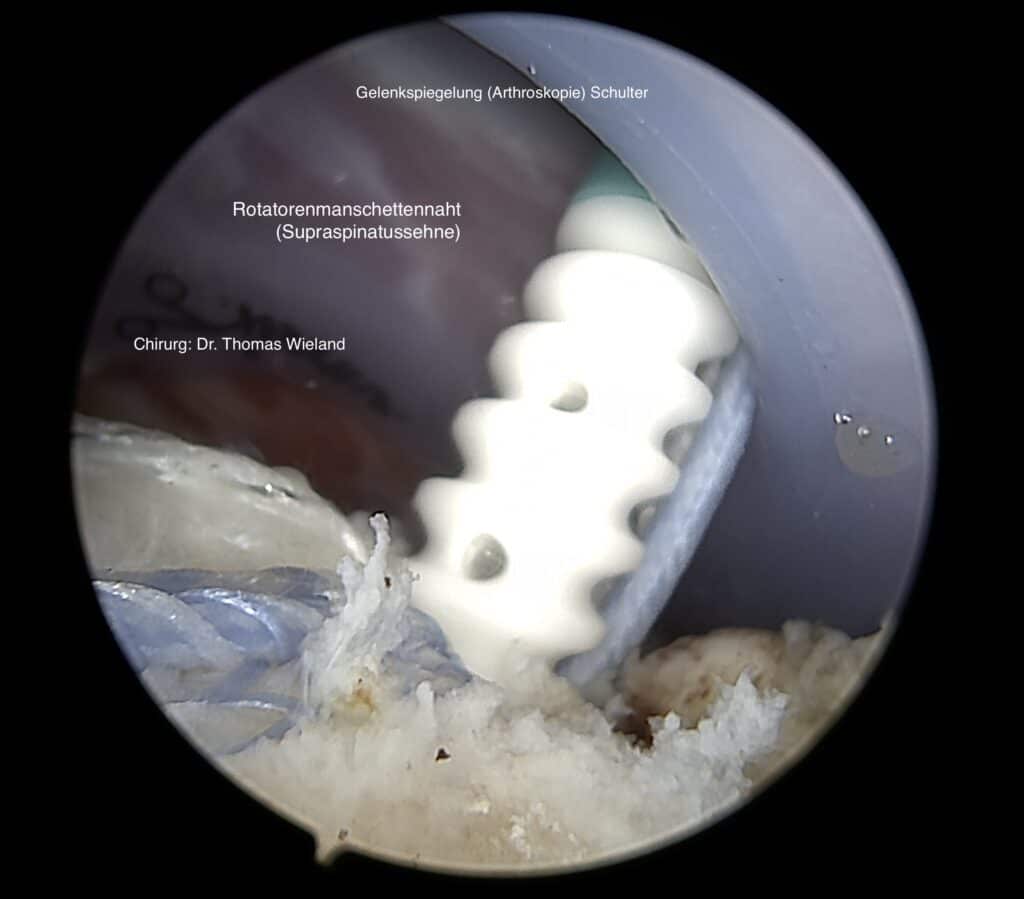

Therapiemöglichkeiten für Schulterverletzungen an der Rotatorenmanschette

Werden kleine Läsionen festgestellt, so können diese zumeist unter fachkundiger Einzelheilgymnastik behandelt werden, denn das erste Ziel zur Behandlung von Schmerzen und Verletzungen an der Schulter ist stets die „Konservative Therapie“. Größere Risse im Bereich der Rotorenmanschette erfordern jedoch häufig eine chirurgische Sanierung.